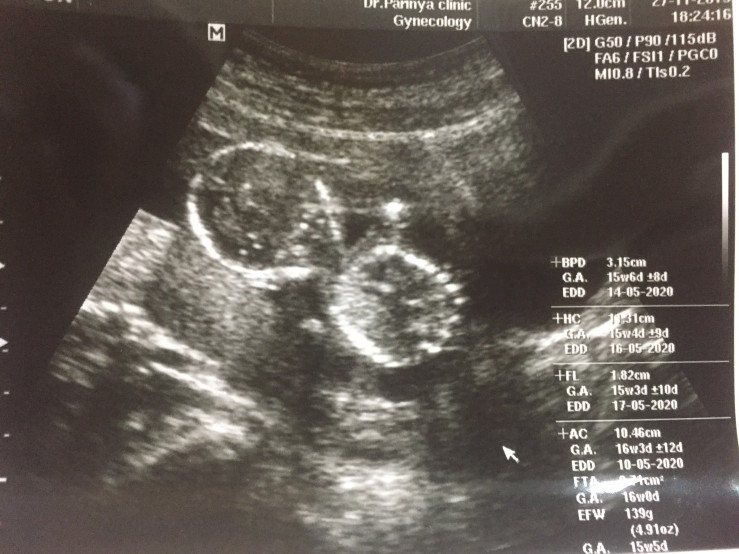

ตอน 16w เห็นเพศแล้วค่ะ